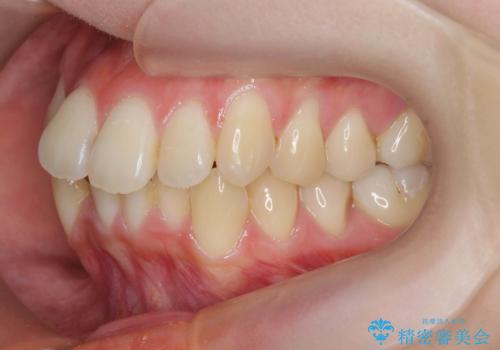

前歯のがたつきをマウスピース矯正できれいに!

- 目立つ前歯のがたつきを改善したい、と矯正治療を希望され来院されました。

今回の治療ではシミュレーションでしっかりと検討した結果、下顎は前歯を1本抜去し仕上げる治療計画としました。